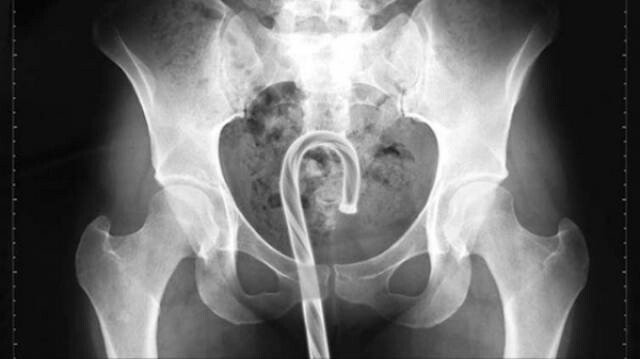

4. Карамельная трость